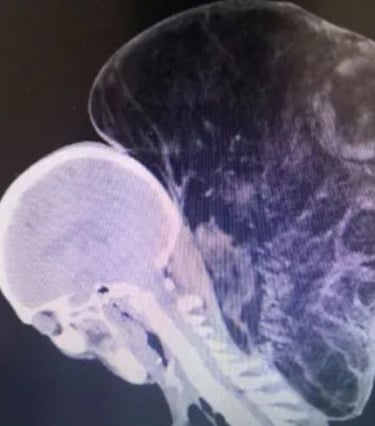

The photos — which you shouldn’t look up over breakfast — show a man whose neck bulges outward like a swollen balloon. It’s soft, rounded, not malignant or monstrous in the cinematic sense. Just there. Lurking in plain sight, tolerated the way we tolerate slow internet or chronic back pain or governments that barely function.

Medical experts who examined the case noted that lipomas can reach enormous sizes when left unchecked. The body doesn’t see them as threats, so the immune system shrugs. The man’s was roughly the size of a basketball, weighing nearly fifteen pounds. It had its own blood vessels — a freeloading roommate metabolically tethered to him.